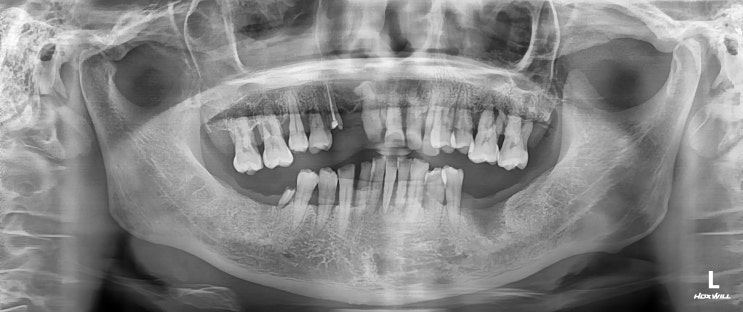

[헬리오시티 치과] 치아 뿌리 염증 신경치료 후 회복

안녕하세요 수서역치과 문정도 치과 수서서울삼성치과 원장 이재현입니다 오늘은 신경치료 후 회복한 환자...